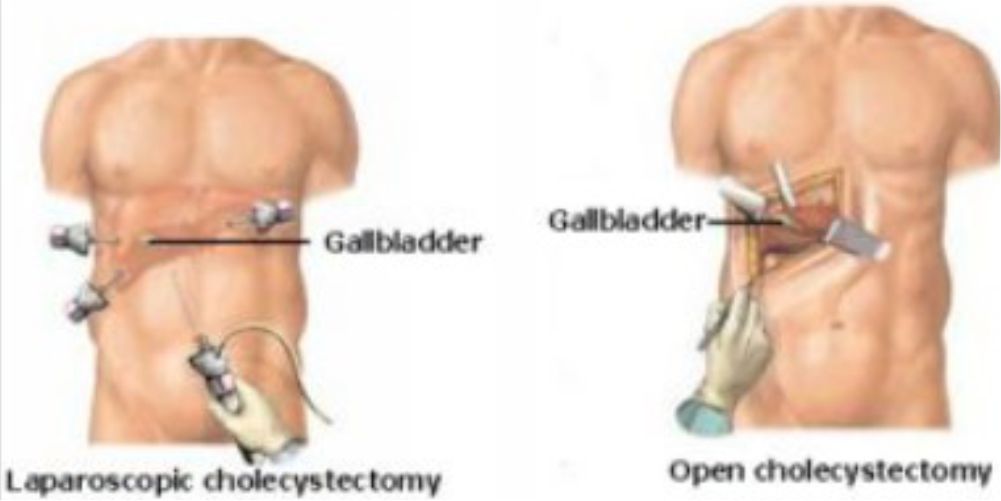

It is often best to leave gallstones alone if there are no symptoms. Symtomatic patients need surgery

Surgery

Keyhole surgery is now the most common way to remove a gallbladder. The medical term for this operation is laparoscopic cholecystectomy.

Rarely, if there are severe adhesions or unsafe to proceed with laparoscopic surgery, the operation may be converted to a traditional open cut method.

❈ WHAT ARE THE RISKS OR COMPLICATIONS OF THE SURGERY?

- Bleeding

- Damage to the blood vessels that go to the liver

- Infection in your belly

- Injury to the common bile duct

- Injury to the small intestine

- Pancreatitis (inflammation in the pancreas)

❈ AFTER THE PROCEDURE

If you do not have any signs of problems, you will be able to go home next day when you are able to drink liquids easily. If there are any problems like bleeding, or the patient is in a lot of pain, or a fever, you may need to stay in the hospital longer

❈ Are there any symptoms after a gallbladder is removed?

Some people who have had their gallbladder removed may develop mild abdominal pain or bloating from time to time.

❈ When will I be able to join work?

You need to take rest for 2-3 days at home (Not bed rest). Most people can join back work within 3-10 days.

Skin stiches would generally dissolve by itself. However, sometimes, sutures may need to be removed after 7-10 days.